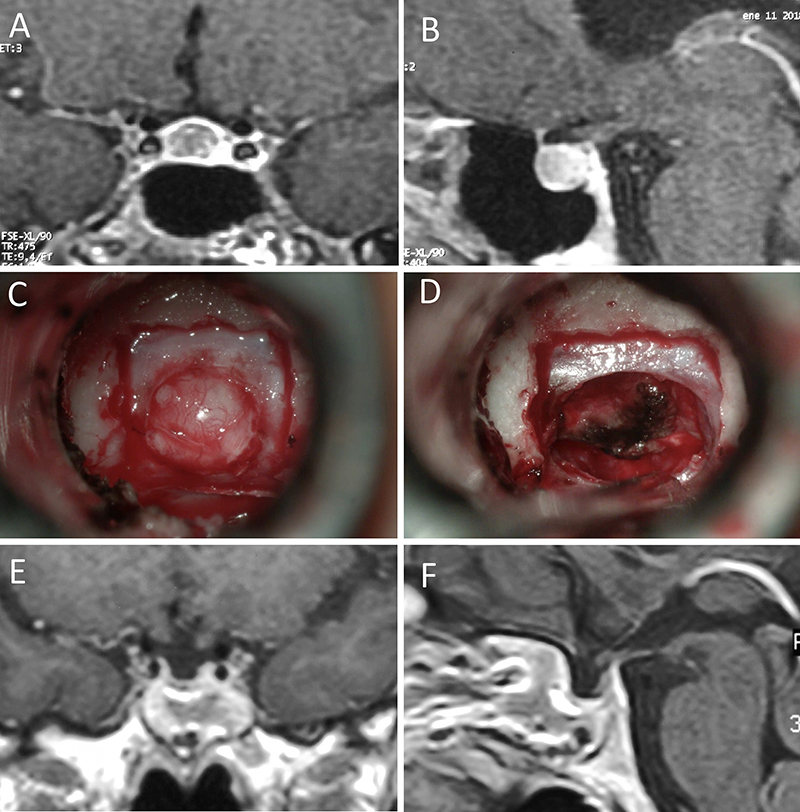

Figura 2: Macroadenoma no funcionante en mujer de 31 años. La paciente presentó en el preoperatorio déficit visual que mejoró tras la cirugía. A-B: RM preoperatoria; C-D: intraoperatorio; E-F: RM postoperatoria.